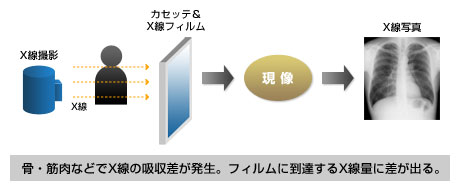

X線写真では、fig1のようにX線フィルムが入ったケースとなるカセッテを患者さんにあてがい、X線を照射して体の構造物(骨や筋肉など)のX線吸収差(吸収コントラスト)を画像情報としてフィルムに記録。現像処理をへてX線写真が仕上がります。

fig1 X線写真撮影(アナログ)